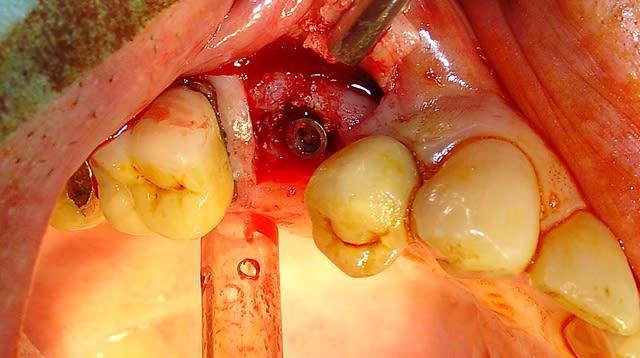

Patient ayant eu une EIMCI avec pilier Peek en ....2011!

Ces piliers ne sont pas fait pour encaisser les forces de mastication. La sentence est tombé: Fracture dans l'implant du piler 4 ans après. (3 premières photos)

Après des tentatives infructueuses de retirer la partie "soudée" dans l'implant la décision fut prise de remplacer cet implant. Il est parfaitement ostéointégré et dans ce cas ceux qui en ont posé savent qu'il impossible de le dévisser sans fracture osseuse même lors de son placement.

Il existe 2 solutions pour le retirer la piezzo ou le trépan.

J'ai donc choisi cette dernière solution très rapide.